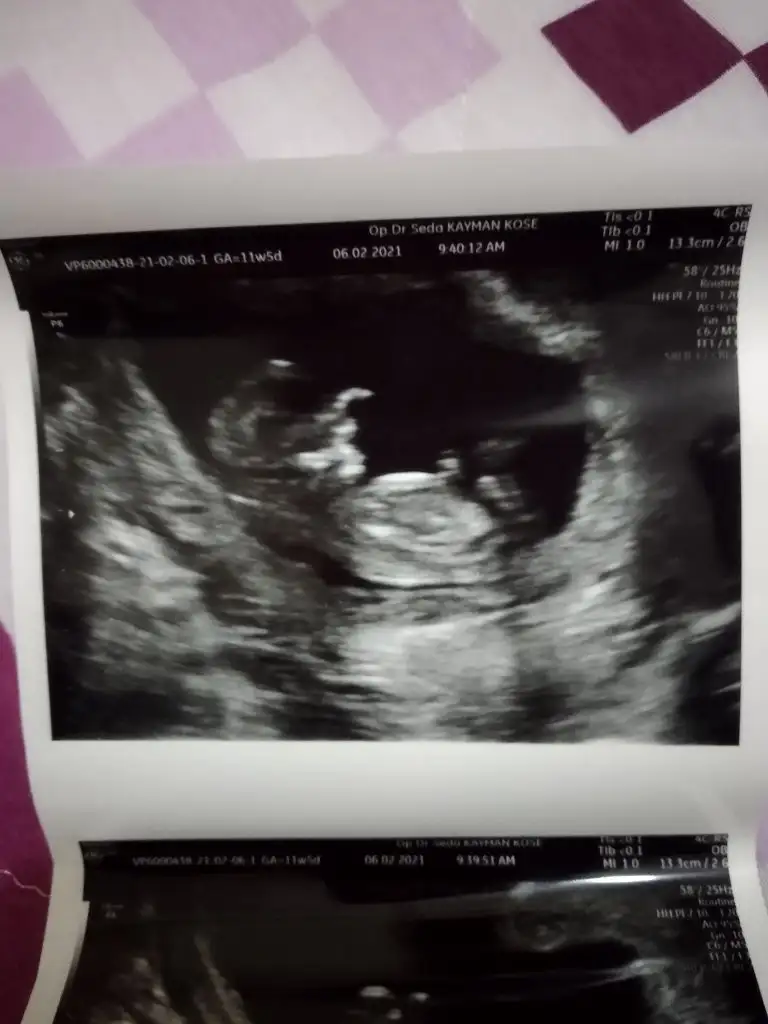

Erkek gibi sanki diyorumMerhaba doktor bi tahminde bulundu fakat siz ne düşünüyorsunuz merak ediyorum@Ikra meyra

Evet doktorda erkek gibi görüyorum dediErkek gibi sanki diyorumönceki usglerde kız sanki demiştim

Buna göre erkek görünüyor ama en iyi 11 12 13 haftalar olmalıMerhabaIkra meyra , benim ultrason görüntülerime de bakabilir misiniz lütfen?

Teşekkür ederimBuna göre erkek görünüyor ama en iyi 11 12 13 haftalar olmalı